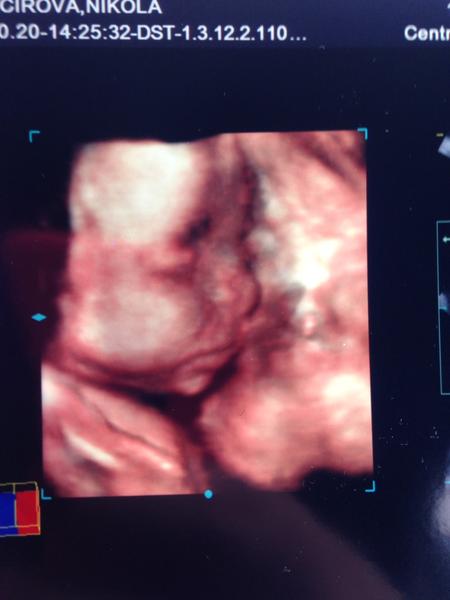

@tercasv ony ty cizí fotky na internetu jsou něco jiného, než když pak člověk vidí toho svého cvrčka 🙂 Mě tedy zase tak moc neoslovily přímo ty fotky - byť se nám povedly docela hezky, ale líbil se mi ten zážitek. Je vidět, jak se tam miminko tváří, jak zívá, dělá ksichtíky........🙂

Za mě fajn cesta do hlubin ...maminčina bříška - moc me bavilo, když jsem pak našla fotku ze 3D a fotku reálnou, které byly témeř totožné - tvář, výraz......

Musím říct, že to bylo super. Přesto, že nejsem zrovna hubená a mám placentu na přední straně, tak bylo mimčo krásně vidět. Oproti těm skoro mazaninám od gynekologa nesrovnatelné....

@tercasv Ja od toho moc neocekavala, premluvil me manzel, ze to zkusime, ze bychom treba litovali. Malej se nechtel ukazat oblicejem, takze jsme si dobre prohledli jeho zadek a naprosto presne vedeli, ze to bude kluk🙈 Pak se ale ukazal a stalo to za to. Mam fotku, kterou mam stale vytavenou na stole a rada se koukam, jak si byl po narozeni podobny, vcetne jeho mimiky😀 U me to tedy predcilo ocekavani, nejen ten vysledek, ale i ten zazitek byl fajn😀.

Stojí - ale až tak v tom cca 23-28 týdnu 🙂 to už je krásně vidět obličejík. Já mám od dcery i syna i moc pěkná videa 🙂